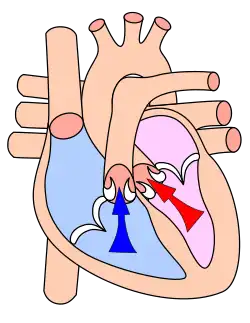

Le septum évite le passage direct du sang. Les valves assurent le passage unidirectionnel coordonné du sang depuis les atria vers les ventricules. Le cœur droit est dit veineux (ou segment capacitif), et le cœur gauche est dit artériel (ou segment résistif). Les parois des ventricules sont plus épaisses, et leur contraction est plus importante pour la distribution du sang contre la résistance artérielle.

Du sang appauvri en oxygène par son passage dans le corps entre dans l'atrium droit par trois veines, la veine cave supérieure (vena cava superior), la veine cave inférieure (vena cava inferior) et le sinus coronaire. Le sang passe ensuite vers le ventricule droit. Celui-ci le pompe vers les poumons par l'artère pulmonaire.

Après avoir perdu son dioxyde de carbone dans les poumons et s'y être pourvu de dioxygène, le sang passe par les veines pulmonaires vers l'oreillette gauche. De là le sang oxygéné entre dans le ventricule gauche. Celui-ci est la chambre pompante principale, ayant pour but d'envoyer le sang par l'aorte vers toutes les parties du corps.

Le ventricule gauche est bien plus massif que le droit parce qu'il doit exercer une force considérable pour forcer le sang à traverser tout le corps contre la pression corporelle, tandis que le ventricule droit ne dessert que les poumons.

Diastole et

Systole auriculaire

Systole ventriculaire

La fréquence cardiaque au repos chez l'Homme est de 60 à 80 battements par minute, pour un débit de 4,5 à 5 litres de sang par minute. Au total, le cœur peut battre plus de 2 milliards de fois en une vie. Chacun de ses battements entraîne une séquence d'événements collectivement appelés la révolution cardiaque. Celle-ci consiste en trois étapes majeures : la systole auriculaire, la systole ventriculaire et la diastole :

- Au cours de la systole auriculaire, les oreillettes se contractent et éjectent du sang vers les ventricules (remplissage actif). Une fois le sang expulsé des oreillettes, les valves auriculo-ventriculaires entre les oreillettes et les ventricules se ferment. Le sang continue tout de même à affluer dans les oreillettes. Ceci évite un reflux du sang vers les oreillettes. La fermeture de ces valves produit le son familier du battement du cœur.

- La systole ventriculaire implique la contraction des ventricules, expulsant le sang vers le système circulatoire. En fait, dans un premier temps, très bref, les valvules sigmoïdes sont fermées. Dès que la pression à l’intérieur des ventricules dépasse la pression artérielle, les valvules sigmoïdes s'ouvrent. Une fois le sang expulsé, les deux valves sigmoïdes - la valve pulmonaire à droite et la valve aortique à gauche - se ferment. Ainsi le sang ne reflue pas vers les ventricules. La fermeture des valvules sigmoïdes produit un deuxième bruit cardiaque plus aigu que le premier. La pression sanguine augmente.

- Enfin, la diastole est la relaxation de toutes les parties du cœur, permettant le remplissage (passif) des ventricules (plus de 80 % du remplissage dans les conditions usuelles), par les oreillettes droite et gauche et depuis les veines cave et pulmonaire. Les oreillettes se remplissent doucement et le sang s'écoule dans les ventricules.